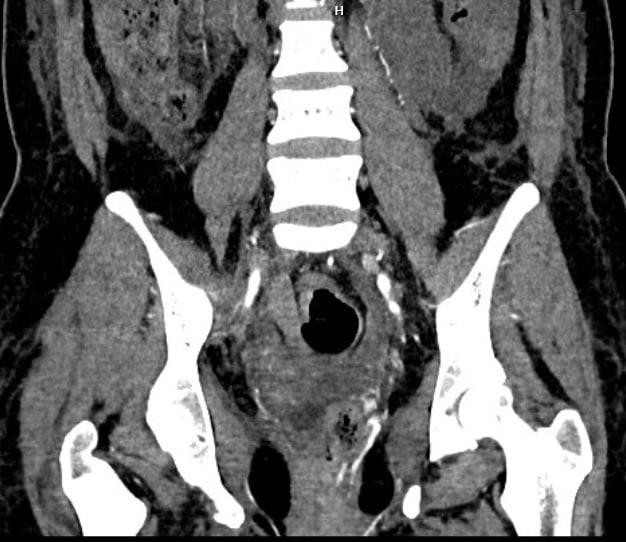

Tại Bệnh viện Bạch Mai, các bác sĩ của Trung tâm Cấp cứu A9 và Trung tâm Điện quang lập tức hội chẩn cấp cứu để đưa ra phương án chẩn đoán và điều trị cho người bệnh. Kết quả chụp cắt lớp điện toán đa lớp cắt (MSCT) cho thấy bệnh nhân bị tổn thương chảy máu từ mạch máu quanh trực tràng.

Hình ảnh thoát thuốc vị trí động mạch tử cung trái và quanh trực tràng của bệnh nhân (Ảnh - BVCC) |